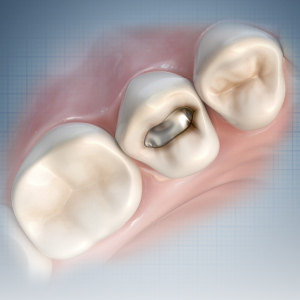

Early Diagnosis and Treatment of Asymptomatic Vertical Enamel and Dentin Cracks

Samer S. Alassaad, DDS

Wednesday, November 23, 2022

This Compendium eBook offers a continuing education (CE) article that presents a systematic approach for the early diagnosis and treatment of asymptomatic vertical enamel and dentin cracks based on current evidence. Download to earn 2 FREE CEU now!